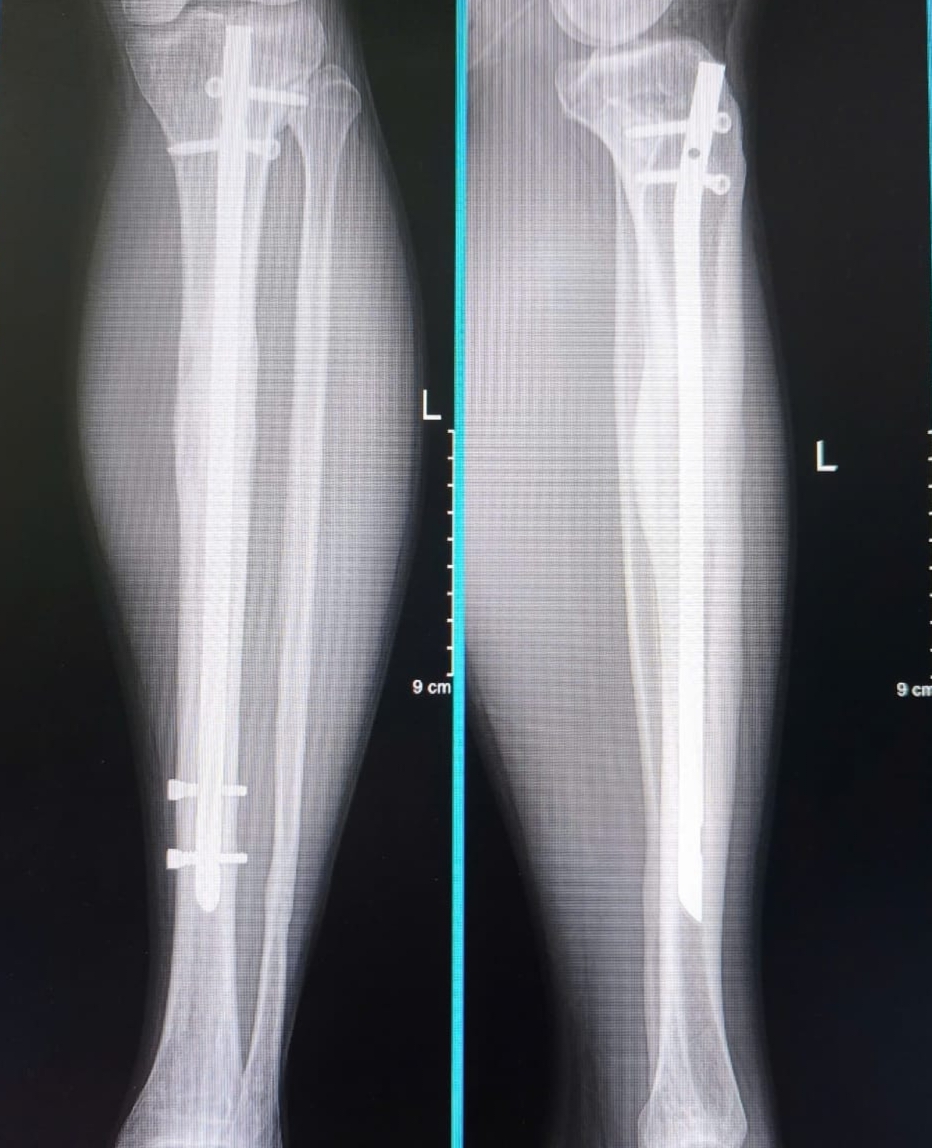

Part 4, ending the lengthening: The time had come where I had reached my desired length. I had opted to go from 7cm down to 6.7, because this was around 20% of my original tibial length. There were however patients who went very much upwards of 7cm, I had met one and we got along quite well. You then stay in your frame for a while longer as the callus (the regenerative structure of your bone) continues to heal. Xrays at this time revealed it as mostly translucent compared to the strong milky white color of the developed bone around it. Eventually I was cleared for frame removal. I knew it’d be a relief to get these things off, but as I was prepped for my second surgery, I ended up crying, I was really fed up with the whole ordeal. The hospital setting, and going in again for another operation really brought the weight and considerations back, but I knew the most challenging parts were behind me. I’ve got to say, the freedom from the frames is amazing, you’re not worried about bumping them into anything, you can roll around in bed, sleep easier, and you start to make the jump from stroller to crutches. From here you gain a whole new degree of freedom, everyday I spent time strolling back and forth with the crutches. Around this time I was transferred to the apartment with the pool and courtyard, and that courtyard became my little slice of heaven. I’d just walk it with crutches around and around, the security guard got so accustomed to my little outings that he introduced himself and told me I was making good progress. One night I had a breakthrough, I was sitting on my bed, practicing these little squats when I stood shakely up, and from there took a step, and then another, sure my gait and posture was far from normal, but my steps felt steady enough that I could just keep on moving on even flooring, I smiled so much just being able to go back and forth without tools for the first time in what felt like forever, and I knew the end was around the corner.

Part 7, Nail removal and then end of my journey: writing this as of now, I am returning for my nail removal. It is a bit surreal visiting the original hospital, greeting and meeting other patients in the middle of their lengthening and being reminded of what was my reality for what felt like so long. But walking up and shaking the hands of patients, none of them realised I’d gone through this until I pulled up my pants to show them the scars. Getting my Xray done, I was happy with the results, the bone of where my osteotomy and distraction took place was as opaque as that of the original bone, the vector of the bone to my eyes also matched the original, a bit thicker in some places, but it’s quite a marvel to see what the human body is capable of in terms of skeletal regeneration. There’s a bit of nervousness to go on to the operating table again, but mostly excitement to be done, to not worry about the complications of having this metal hardware in your legs long term, and utmost a faith that the nail removal is a vastly more simple procedure then inserting it along with the frames and stretching your legs out, the worst part it over, and I’m grateful to close the chapter on this journey, you’re not the same person before and after, I never really visited the limb lengthening forum or watched any of Victor’s videos after I returned home. Your mind goes to different focuses and motivations because you have completed what you set out for. I will post an update on the intricacies of the nail removal, and try my best to answer any further questions, but the Limb Lengthening forum isn’t something I intend to visit again regularly, it is a part of what is quickly becoming the past for me. Images and videos are attached for those curious.